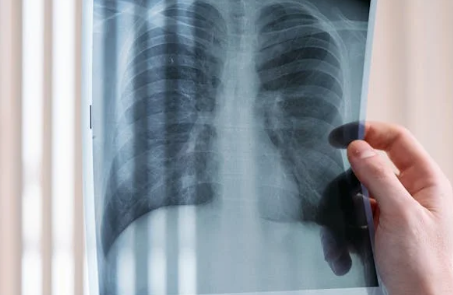

肺大泡(肺大疱)虽看似局部问题,但其潜在影响却可能蔓延至整个呼吸系统乃至全身,需引起足够重视。

随着肺大泡体积增大或数量增多,周围健康的肺组织会持续受到压迫,导致肺泡无法充分进行气体交换。这不仅会引起咳嗽、胸闷、活动耐力下降等症状,还可能进一步削弱肺功能,甚至诱发或加重慢性支气管炎、肺气肿、哮喘等疾病。在进展较快的病例中,还可能逐渐演变为慢性阻塞性肺疾病或呼吸衰竭。

肺大泡破裂是自发性气胸最常见的原因。一旦破裂,气体进入胸膜腔,肺部受压塌陷,患者可能突发剧烈胸痛与呼吸困难,属于呼吸科急症,需立即就医,否则可能危及生命。

随着病情进展,肺大泡可能引发身体水电解质紊乱与酸碱失衡,进而影响心、肝、肾等重要器官的功能。严重时甚至可能诱发多器官功能不全或衰竭,成为疾病发展的最大风险。